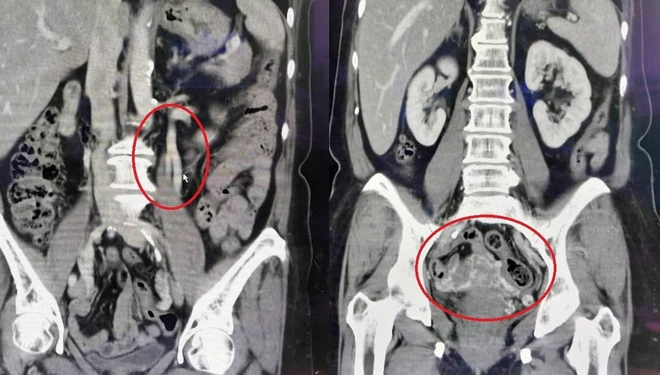

在排除可能導致骨盆腔疼痛的疾病後,仍找不出異常原因的病人,可考慮接受超音波或電腦斷層檢查骨盆腔內靜脈是否擴張。若為骨盆腔鬱血症候群,透過電腦斷層可發現生殖器官旁邊出現大量靜脈,如同骨盆腔裡的靜脈曲張。

王女士透過檢查發現左側卵巢靜脈有擴大現象,且子宮及雙側卵巢旁有大量靜脈出現。(圖片:大千綜合醫院)